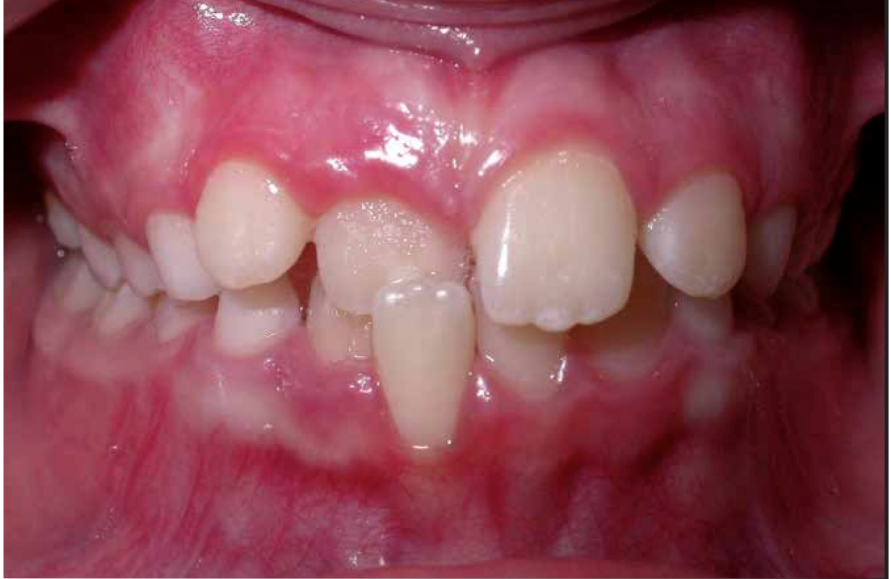

Khớp cắn chéo quá sâu có thể tình cờ gây ra loét mô mềm, những trường hợp này nhu cầu thẩm mỹ thì nhỏ nhưng vấn đề loại bỏ nguyên nhân gây chấn thương mô mềm thì lớn. Ai nên được điều trị chỉnh nha? Phần lớn điều trị chỉnh nha được tiến hành vì nhu cầu thẩm mỹ và lợi ích mà mỗi bệnh nhân nhận được từ việc điều trị sẽ phụ thuộc vào mức độ trầm trọng của mức độ sai khớp cắn và nhận thức của bệnh nhân về vấn đề này. Một số cá nhân có thể có sự lệch lạc ở mức độ quá rõ ràng làm ảnh hưởng trầm trọng tới gương mặt của họ tuy nhiên họ cũng chẳng quan tâm đến và không cần điều trị nếu bác sỹ không có cách thuyết phục. Bác sĩ lâm sàng có thể đưa ra lời khuyên về phương pháp điều trị cho bệnh nhân nhưng cũng không nên yêu cầu họ một cách cứng nhắc mà nên để cho họ có thời gian ngồi lại và suy nghĩ để đưa ra quyết định cuối cùng hợp tác với bác sỹ điều trị. Lệch lạc khớp cắn mức độ nhẹ nên được điều trị với sự cẩn trọng vì khả năng tái phát sau khi điều trị. Các bậc phụ huynh có thể có rất nhiều yêu cầu khác nhau nhưng các bác sĩ lâm sàng nên tiếp cận những vấn đề này một cách cẩn trọng và chỉ tiến hành điều trị khi nó đem lại lợi ích tốt nhất cho bệnh nhân. Điều thiết yếu nhất cần nhớ là phụ huynh và bác sĩ cần phải nhận thức rõ về những hạn chế cũng như sự đòi hỏi nhiều thời gian của việc điều trị chỉnh nha. Kế hoạch điều trị nắn chỉnh răng Trong quá trình phát triển của bộ răng người, có thể chia làm ba giai đoạn chính như sau: giai đoạn răng sữa, giai đoạn răng hỗn hợp và giai đoạn răng vĩnh viễn. Sau đây là một số gợi ý những trường hợp nào cần và nên điều trị theo các giai đoạn của bộ răng: Kế hoạch điều trị ở hàm răng sữa Lý do điều trị: điều trị nắn chỉnh răng ở hàm răng sữa vì lý do sau: (1) loại bỏ các cản trở đến sự tăng trưởng bình thường của mặt và cung răng. (2) duy trì hoặc phục hồi lại chức năng bình thường Các trường hợp cần phải điều trị: a) Cắn chéo phía trước và sau.

c) Răng mọc sai vị trí gây cản trở phát triển chức năng cắn khớp bình thường, gây rối loạn mọc răng hoặc há ngậm miệng, hoặc gây ảnh hưởng xấu đến sức khỏe răng miệng. d) Răng thừa có thể là nguyên nhân gây sai khớp cắn e) Khớp cắn chéo ở răng vĩnh viễn